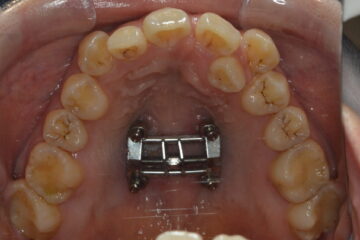

上顎急速拡大装置(MSE)

現在、須川さんはMSE(上顎の拡大装置)を2回目に設置する準備期間。

2025年10月(治療前)

2025年12月